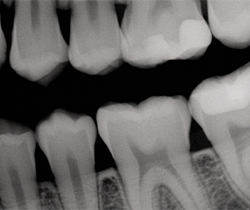

After occlusion is adjusted and restorations are finished and polished with OptraPol polishing cups and points (Ivoclar Vivadent), final radiographs and photos are taken to demonstrate the radiopacity of the material, the ideal interproximal contours and sealed margins, and its monolithic, void-free qualities (Figs. 16-20).

Fig. 20